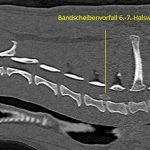

Bandscheibenvorfall beim Hund